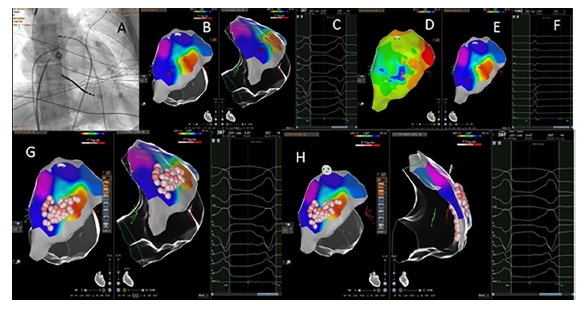

Ablacion endo-epicárdica de taquicardia ventricular en miocardiopatía arritmogénica del ventrículo derecho